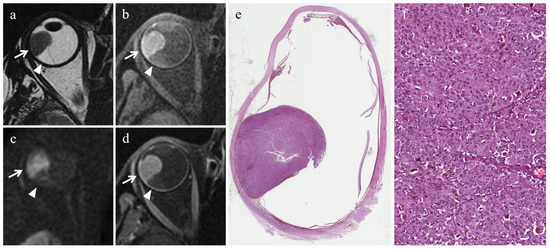

- Foti, P.V.; Inì, C.; Broggi, G.; Farina, R.; Palmucci, S.; Spatola, C.; Liardo, R.L.E.; Milazzotto, R.; Raffaele, L.; Salamone, V.; et al. Histopathologic and MR Imaging Appearance of Spontaneous and Radiation-Induced Necrosis in Uveal Melanomas: Initial Results. Cancers 2022, 14, 215. [Google Scholar] [CrossRef]